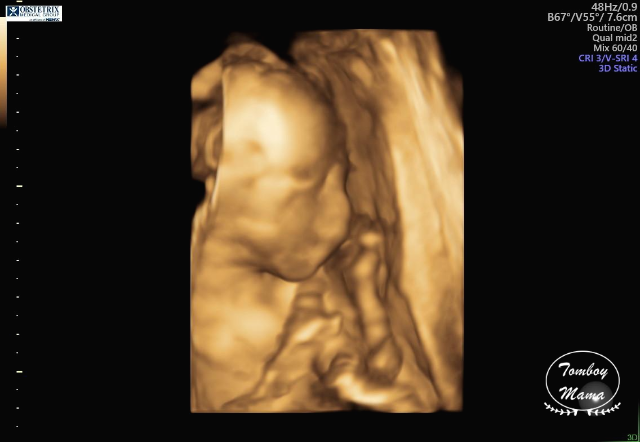

그리고 3D로 만나본 튼튼이. 사진들이 살짝 무섭긴 한데, 나중에 태어난 후의 모습이랑 비교하면 많이 비슷하려나 궁금하다. (찾아보니 입체 초음파 사진으로 생후 모습을 분석해 보여주는 한국 스타트업의 [베이비페이스]라는 프로그램이 있더라고요! 해보고 싶었는데, 25주 이상의 입체 초음파 사진이 필요하다고 해서 전 포기했어요... 저처럼 궁금하신 분들 참고하세요~)